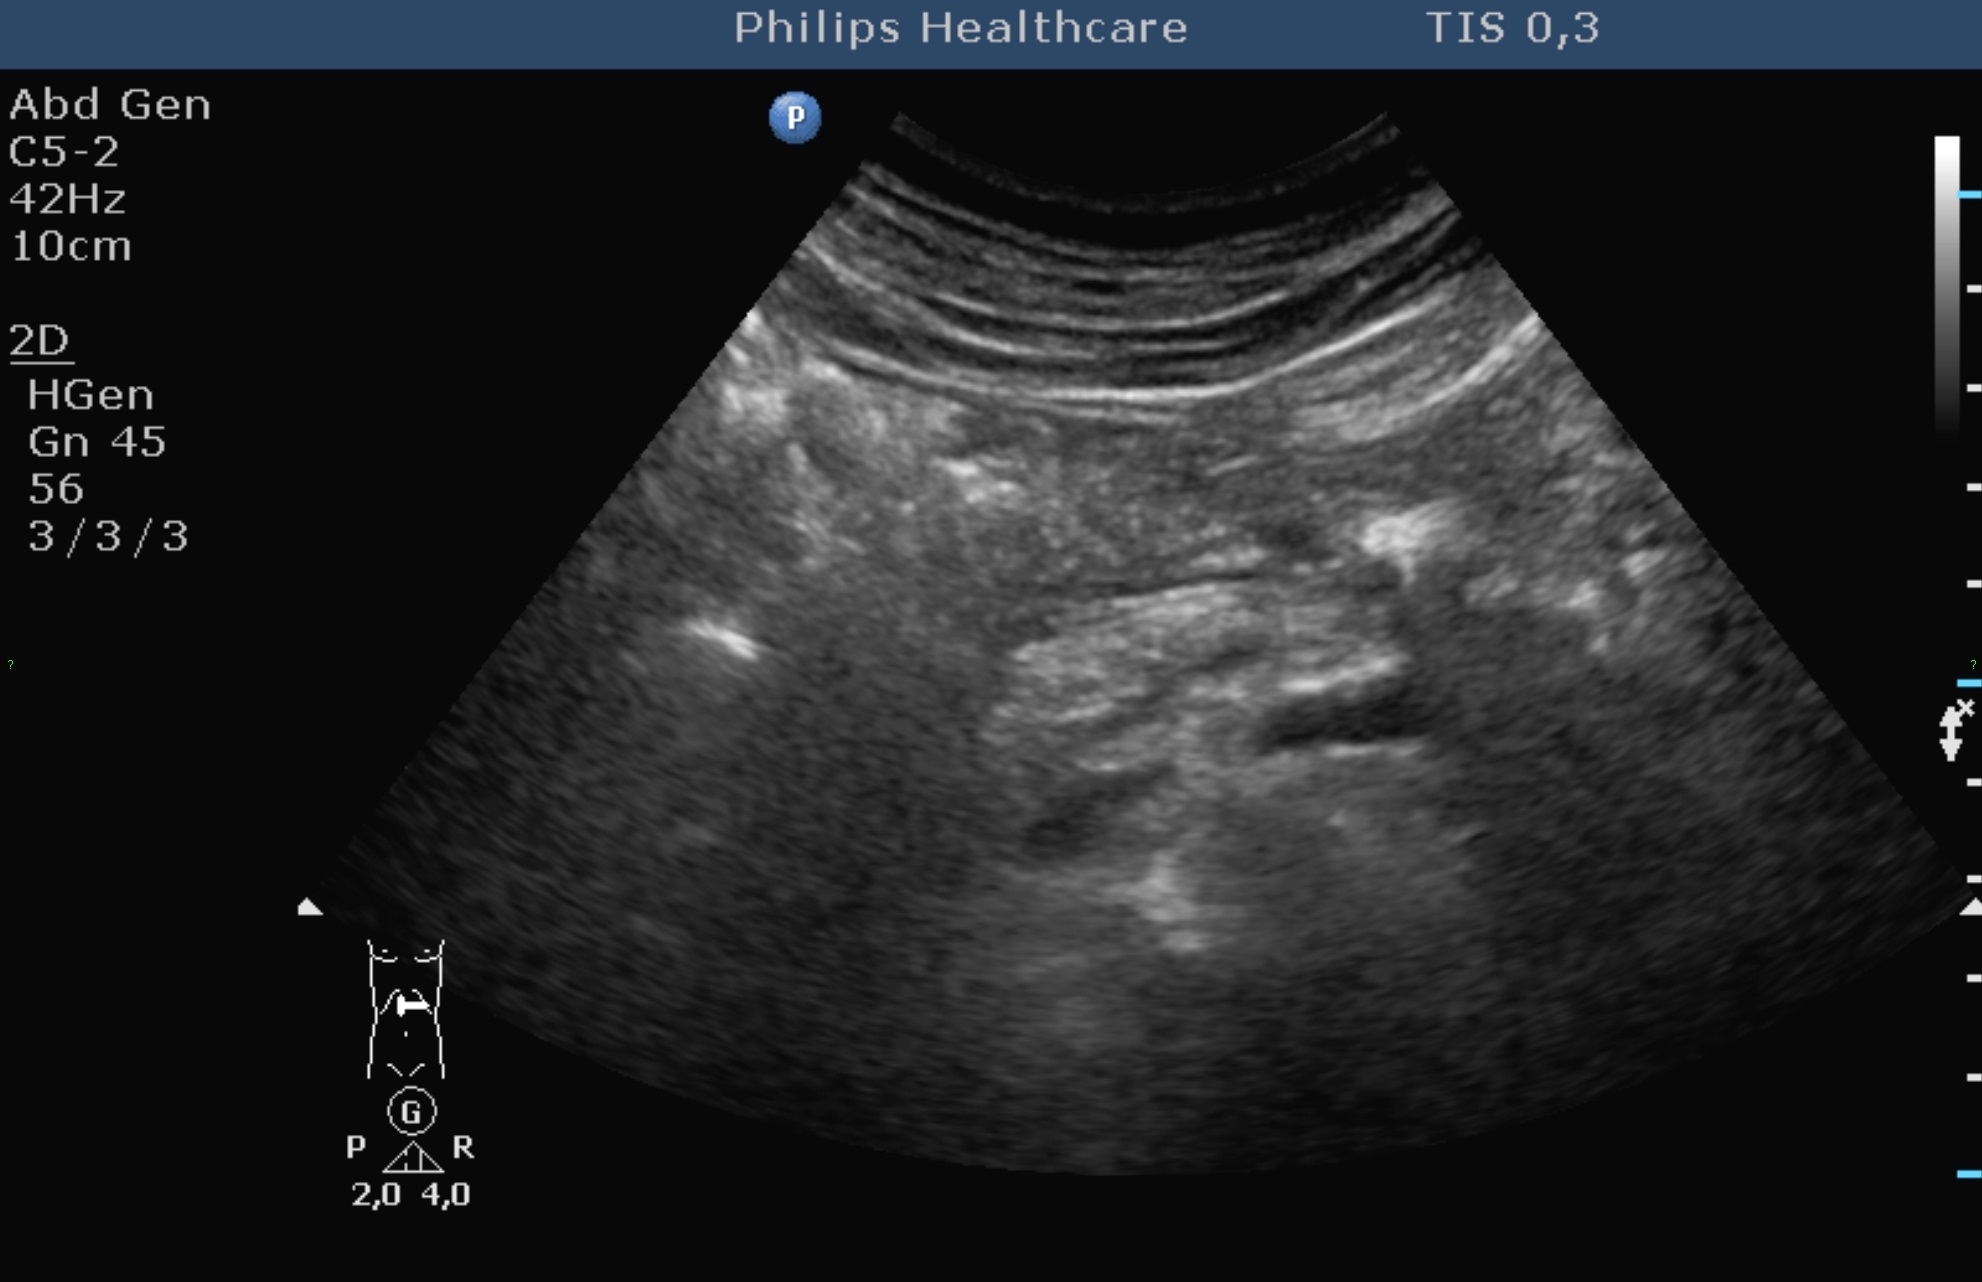

The echogenicity of the normal liver tissue is mildly hyperechoic (Figure 3) due to the intrahepatic connecting tissue structures, small veins, arteries and bile ducts (its echogenicity is principally comparable with the adjacent normal right kidney cortex, the liver has a bit hyperechoic structure than the right kidney, and its echogenecity is principally the same as the spleen's).

Figure 3: Normal liver, 2D US image